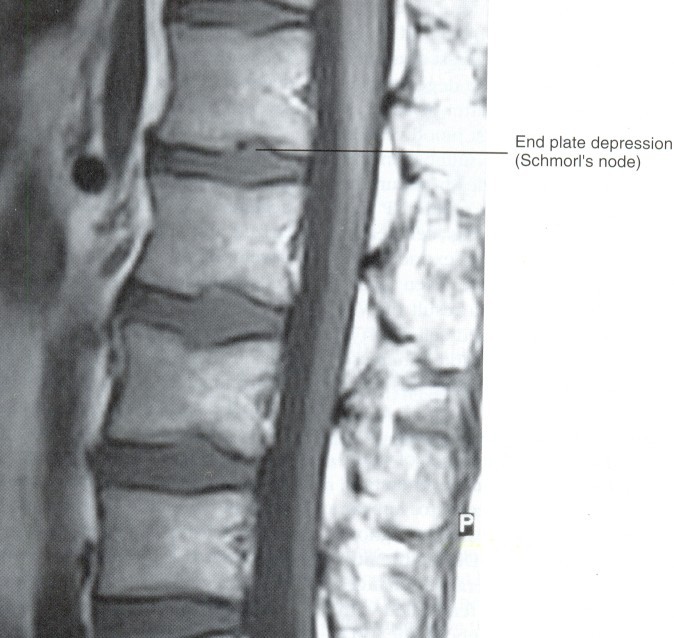

Schmorl's node

Hydrostatic loading of the Nucleus Pulposus (NP) of the IVD causes bulges of the nucleus into the Cartilagenous End Plate(CEP)

fractures of the CEP can occur if the compressive force is great enough.

CEP fracutures, also known as traumatic Schmorl's nodes, have been noted in postmoterm studies as features of disc digeneration

Schmorl's nodes are defined as heerniation of the IVD through the CEP and bony end flate.

these lesions are believed to be associated with trauma and occur most frequently in the lower thoracic and lumbar region